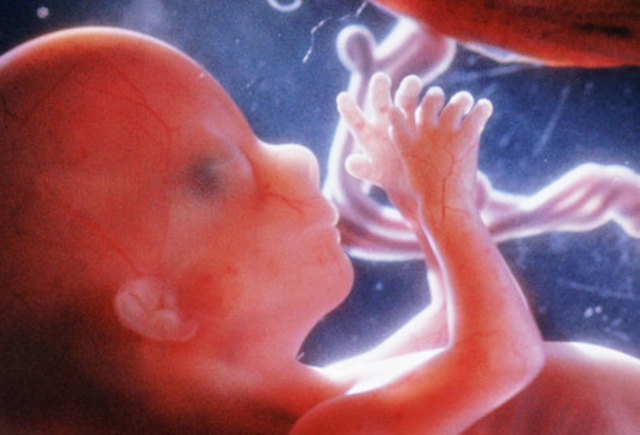

• development at 20 weeks

development at 20 weeks

baby weighs 10 ounces the baby starts sucking thumbs yawn and stretch